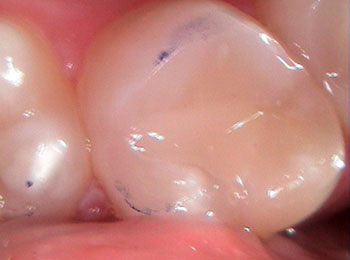

While silver/amalgam fillings are a safe, long-lasting, and trusted dental material — tooth-colored/metal free fillings can provide a strong esthetic alternative. These composite resin fillings are bonded to tooth structure allowing minimal removal of tooth structure making them a very conservative restoration. Materials come in a wide variety of shades to ensure proper color matching and is therefore visually undetectable.

Before decay removal

After decay removal